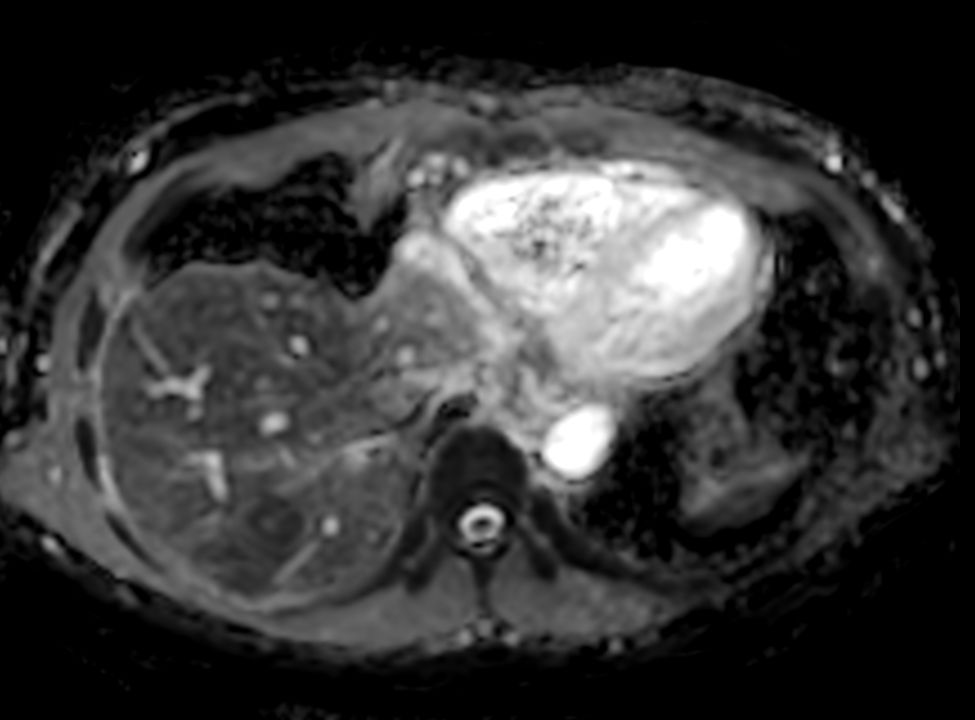

Diffusion b1000 - Free Breathing (VitalEye)

Diffusion b1000 (ADC) - Free Breathing (VitalEye)